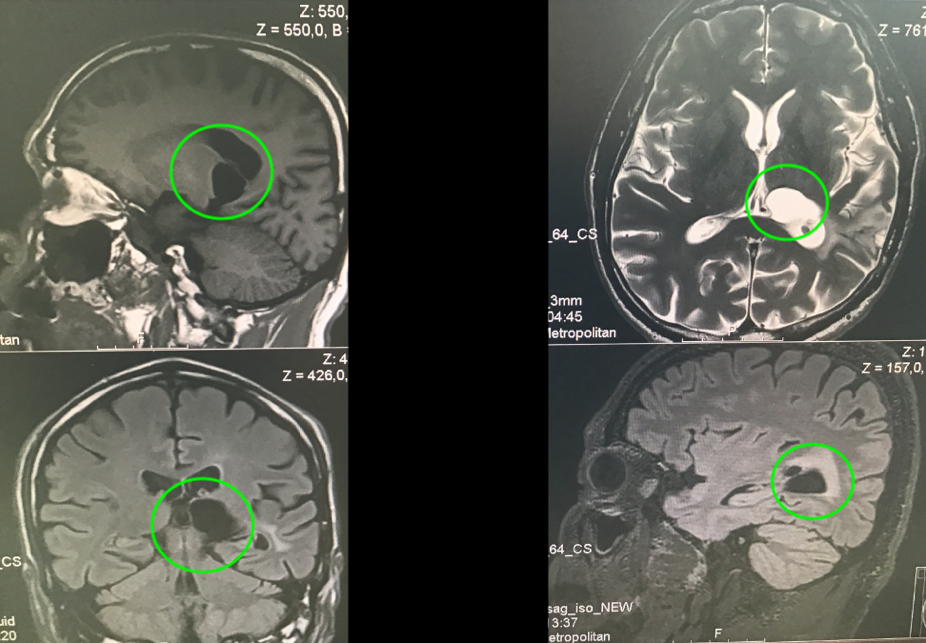

作為鋼琴演奏家、鋼琴老師的Z女士,大約4個月前發(fā)現(xiàn)出右手彈奏不靈活,細致活動限制,頭部右側(cè)和右腳麻木感,也偶有視力模糊、有霧感,起初本以為是太勞累所致,卻不見好轉(zhuǎn),當?shù)蒯t(yī)院就診,在當?shù)蒯t(yī)院發(fā)現(xiàn)丘腦內(nèi)較大占位,考慮膠質(zhì)瘤可能。Z女士而后輾轉(zhuǎn)多處,得知德國Helmut Bertalanffy(巴特朗菲,國內(nèi)病人尊稱“巴教授”)在這領(lǐng)域的豐富成功經(jīng)驗,成功聯(lián)系并進行了二意見咨詢,得到可以手術(shù)全切的回復(fù)后,一家人帶她前往巴特朗菲教授所在的德國漢諾威INI國際神經(jīng)學(xué)研究所進行手術(shù)治療。

丘腦<a href='/jibing/naojiaozhiliu/1803.html' target='_blank'><u>膠質(zhì)瘤手術(shù)</u></a>案例

在5-ALA熒光、術(shù)中神經(jīng)導(dǎo)航和術(shù)中MRI輔助手術(shù),通過左側(cè)頂枕枕骨開顱術(shù)和顯微外科腫瘤全切手術(shù),手術(shù)順利,無手術(shù)并發(fā)癥?;颊咝g(shù)后當天即拔出氣管插管,無任何問題,轉(zhuǎn)入重癥監(jiān)護室進行觀察1天。術(shù)后當天與術(shù)前相比,右手和手臂仍有輕微的偏癱和輕度運動無力,無言語功能障礙。術(shù)后2天,檢查術(shù)后CT正常,無血腫和明顯腦水腫等,該患者的臨床狀況迅速好轉(zhuǎn),并遷出ICU。術(shù)后3天即在物理治療下增加康復(fù)鍛煉,下地鍛煉,術(shù)后5天即可自行站立行走。在INI住院期間,手細致功能障礙、言語和感覺偏癱均得到好轉(zhuǎn)。右手的細致運動技能也比手術(shù)后開始時明顯好轉(zhuǎn)。